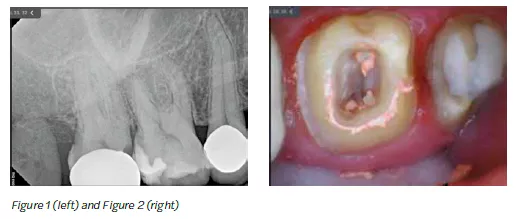

The patient came in for a crown re-do on tooth No. 2 and pain on tooth No.3 (Figure 1).

The patient presented with a failing restoration on tooth No. 2 and caries/decay extending greater than two-thirds occlusal table. The procedure consisted of removal of gross decay, any fractured enamel or old restorations, replacement of tooth structure with a buildup, and placement of a crown to cover and protect the tooth and ensure the patient can return to normal function.